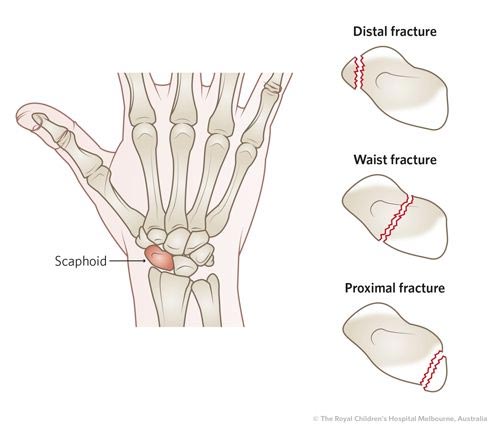

舟骨骨折 Scaphoid Fracture

舟骨骨折是常被忽視的受傷,因為單靠X光未能準確排除,一定要配合醫生的臨床檢查和特別角度的X光及磁力共振才可判斷。舟骨骨折最可怕的併發症是當骨折被忽略和處理不當,會導致舟骨骨枯,最終影響手腕的功能、活動能力以及加速退化。

由於舟骨的血液循環特別慢,愈合時間比其他骨折更費時,需要2至3個月。